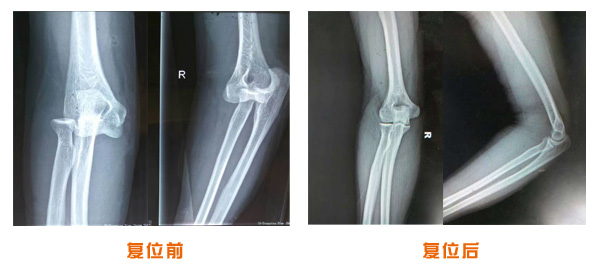

肥城市安駕莊梁氏骨科醫院是一所以梁氏手法正骨配合膏藥為特色的現代化??漆t院。

梁氏骨科術始創于清雍正年間,歷經八代,至今已有三百年歷史。據1929年泰安縣志載“梁瑞圖先生,字增生,號蓮峰,安駕莊人,精岐黃并發明接骨,凡跌打車凡跌打車軋皮不破而碎骨者......【詳細】 |